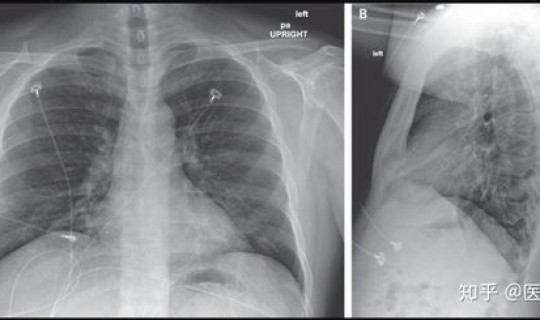

1、新型冠状病毒感染的肺炎患者的临床表现为:以发热、乏力 、干咳为主要表现,鼻塞、流涕等上呼吸道症状少见,会出现缺氧低氧状态。

2、约半数患者多在一周后出现呼吸困难 ,严重者快速进展为急性呼吸窘迫综合征、脓毒症休克 、难以纠正的代谢性酸中毒和出凝血功能障碍。

3、值得注意的是,重症、危重症患者病程中可为中低热,甚至无明显发热 。部分患者起病症状轻微 ,可无发热,多在1周后恢复。多数患者预后良好,少数患者病情危重 ,甚至死亡。